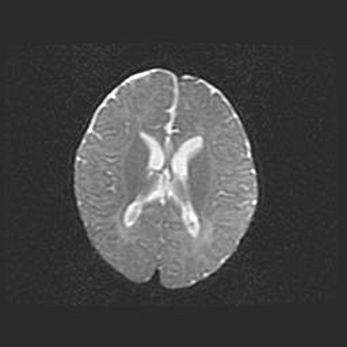

Сообщающаяся гидроцефалия. Кистозная энцефаломаляция головного мозга.

Возраст: 3 месяца 4 дня

Вес: 3100 г

Пол: женский

Окружность головы: 34 см

Срок гестации: 31 неделя

Кистозная энцефаломаляция головного мозга - одна из форм поражения головного мозга в детском возрасте. Характеризуется возникновением множественных и распространённых кист в коре, белом веществе и подкорковых образованиях головного мозга у плодов, новорождённых и детей раннего возраста. Развитие кистозной энцефаломаляции связано с внутриутробной асфиксией и гипотонией, родовой травмой, тромбозом синусов, пороками развития сосудов, инфекциями, сепсисом и другими причинами. Наиболее значимые инфекционные агенты: вирусы простого герпеса, цитомегалии, краснухи, токсоплазмы, энтеробактерии, золотистый стафилококк и другие.